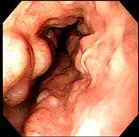

6.內鏡檢查 雖可明確食管穿孔特別是異物損傷的部位,但要切記操作勿粗暴,勿過度充氣,否則可能會使穿孔加重。